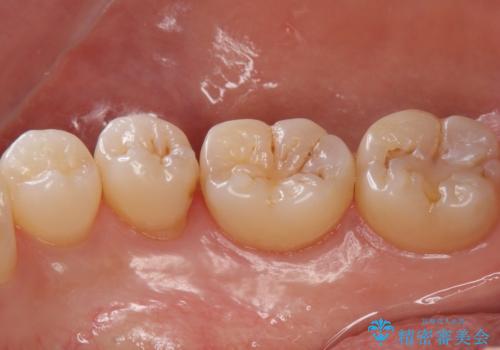

歯と歯の間の虫歯 セラミックインレーでの修復処置

- 検査の結果、歯と歯の間に虫歯が確認された患者様です。

虫歯を除去した後、セラミックインレーで修復処置を行います。

- 右下5 セラミックインレー 77,000円費用は治療当時の料金となります

レントゲン画像では写りにくい小さな虫歯も発見したため、そこも含めた形での修復処置を行いました。